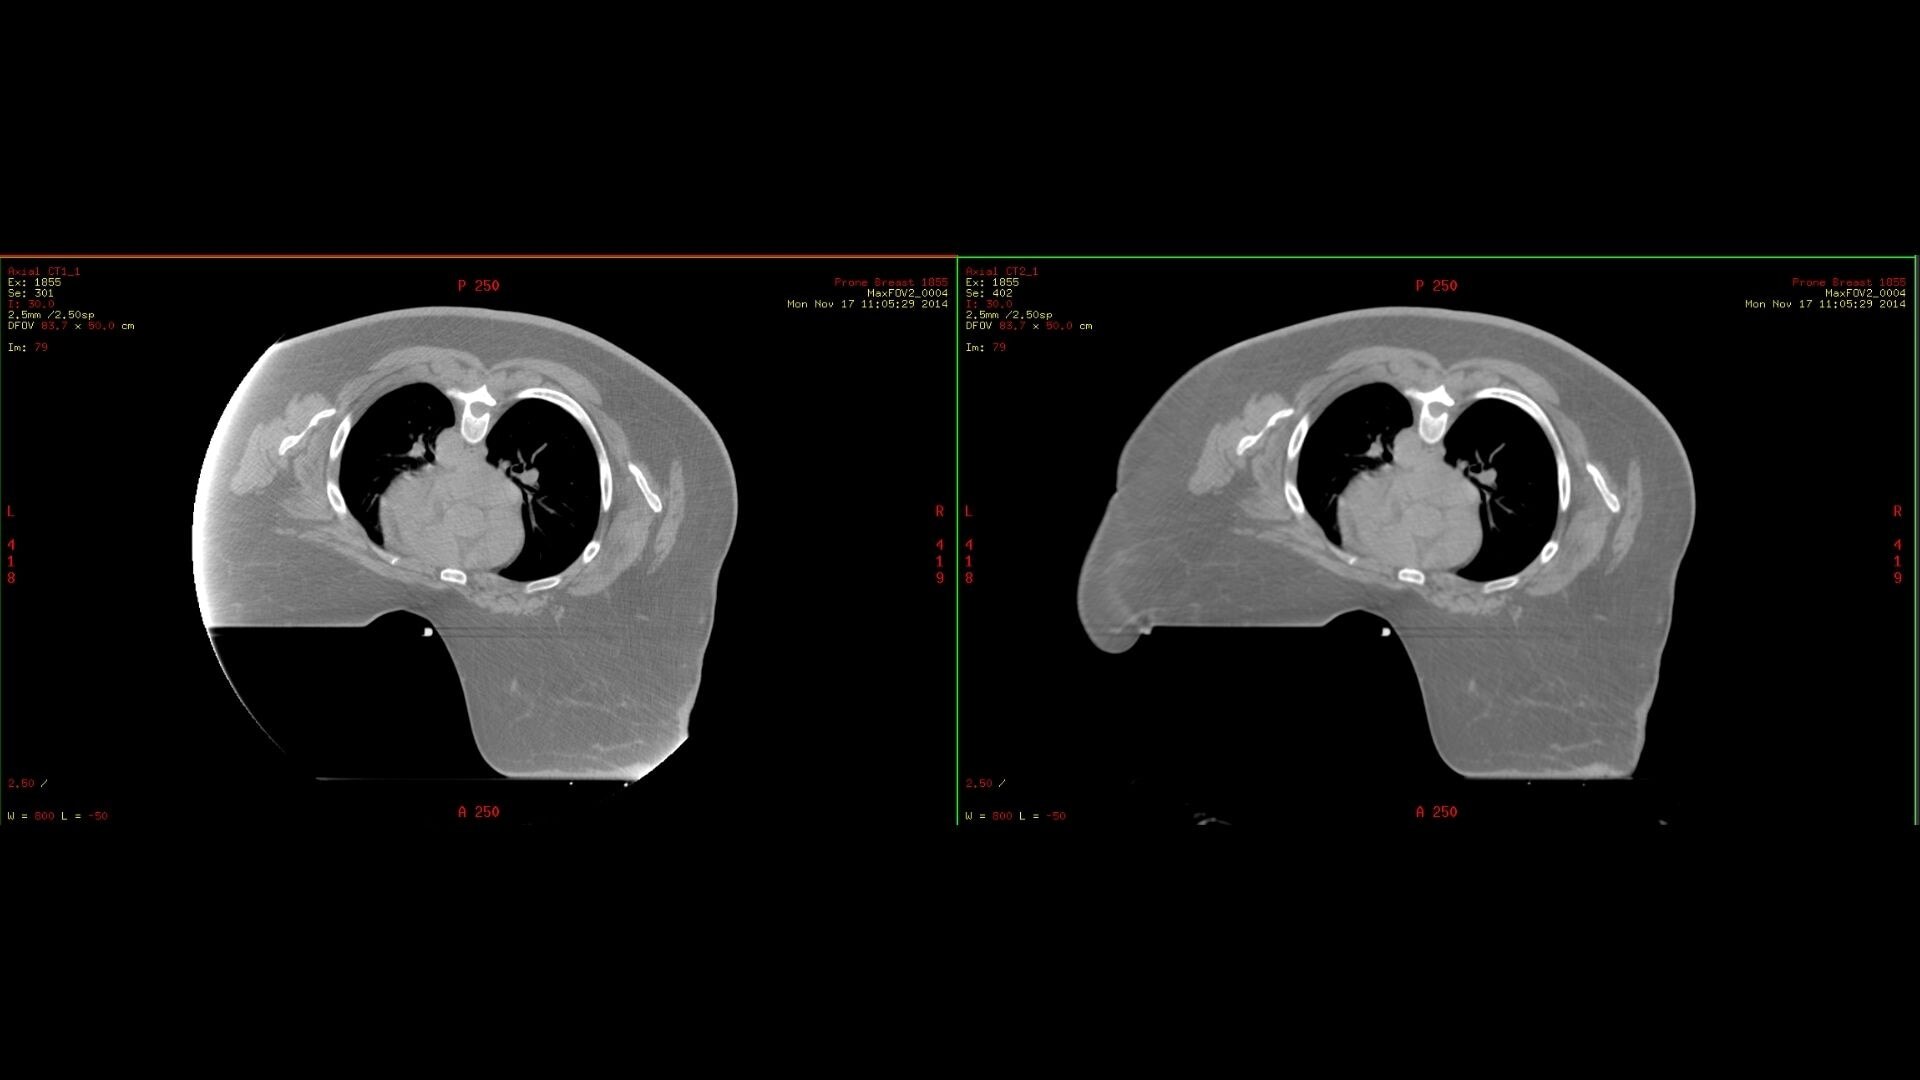

MaxFOV 2

The unique needs of radiation oncology make it important to have image data across the entire bore of the CT simulator. MaxFOV 2 uses GE HealthCare’s proprietary deep learning algorithm to build an extended view up to the edge of the bore. With up to 80 cm extended Display FOV (DFOV), MaxFOV2 allows for less limitations and better image quality that include:

• 2mm skin line accuracy and 40HU CT number accuracy of water from 50cm to 70cm DFOV *

• 3mm skin line accuracy and 60HU CT number accuracy of water from 70cm to 80cm DFOV *

*As demonstrated by phantom testing